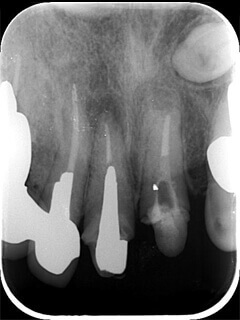

学生の頃には2本と教えられた根管もマイクロスコープで見るとこのように3本目の神経MM根を発見することがよくあります。

9

2つ神経があるように見えます。

10

真ん中にもう一つ隠れていました。

穴が開いてしまっている根管でもMTAを使い封鎖し、隠れてしまった本来の神経をマイクロスコープで見つけることができました。